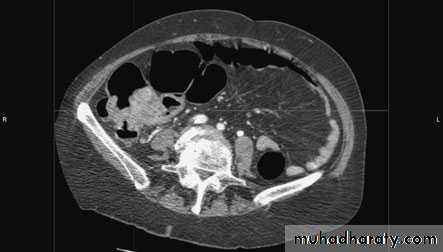

DiagnosisRadiologyAlthough the diagnosis of acute diverticulitis is made on clinicalgrounds, it can be confirmed during the acute phase by computerised tomography (CT). It is particularly good at identifyingbowel wall thickening, abscess formation and extraluminal disease., drainage may be carried out percutaneously. Such anoption may delay or postpone further operative procedures.

ImagingBarium enema will show similar features to those of colonoscopyin the colon. The best investigation of the small intestine is smallbowel enema . This will show up areas of delay anddilatation. The involved areas tend to be narrowed, irregular and,sometimes, when a length of terminal ileum is involved, theremay be the string sign of Kantor. Sinograms are useful in patientswith enterocutaneous fistulae. CT scans are used in patients withfistulae and those with intra-abdominal abscesses and complexinvolvement .Magnetic resonance imaging (MRI) has been shown to be usefulin assessing perianal disease.